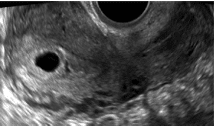

Pseudogestationssæk: Ultralydsfund som ses ved 10-20 % af ekstrauterine graviditeter. Ses som lille opklaring, typisk dårligt afgrænset, ligger ofte midt i kaviteten.

Pseudogestationssæk: Ultralydsfund som ses ved 10-20 % af ekstrauterine graviditeter. Ses som lille opklaring, typisk dårligt afgrænset, ligger ofte midt i kaviteten. Håndteres som PUL.